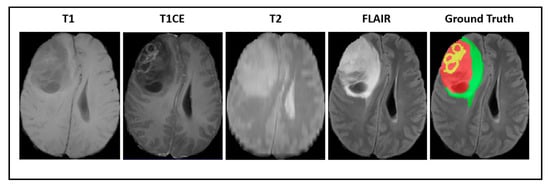

Our experiments were implemented based on the imaging data provided by the Brain Tumor Segmentation Challenge (BraTS2018) [57,58,59]. All of the medical images were provided in 3D volumes with four kinds of MR sequences called native T1weighted (T1), post-contrast T1-weighted (T1CE), T2-weighted (T2), and fluid attenuated inversion recovery (FLAIR). Multimodal scans were acquired from 19 institutions with various clinical protocols and different scanners. Figure 2 shows a visualization of BraTS2018 datasets with tumor masks on each MRI modality.

Figure 2.

A visualization of Brain Tumor Segmentation Challenge (BraTS) datasets with a tumor mask where green illustrates the edema, yellow illustrates the enhancing tumor, and red illustrates the necrotic area.

In this dataset, all modalities were coregistered with the same anatomical template and sampled with a dimension of 1 mm × 1 mm × 1 mm. The MR images of all patients were manually segmented by four experts and verified and approved by experienced neuroradiologists. These labels were annotated based on the intratumoral structures in gliomas. The segmentation results were evaluated based on the tumor subregions, including the whole tumor, the tumor core, and the enhancing tumor as shown in Figure 3. The evaluation was done by uploading the segmented files to the online evaluation system CBICA Image Processing Portal (https://ipp.cbica.upenn.edu). The dataset included 285 patients for the training process and 66 patients for validation. The training datasets can be downloaded from the contest’s official website (http://braintumorsegmentation.org).